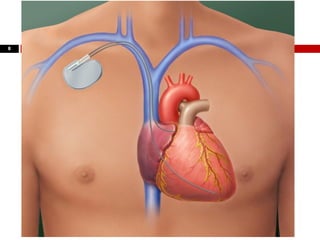

 A passagem de marca-passo transvenoso é outra

indicação de punção venosa central.